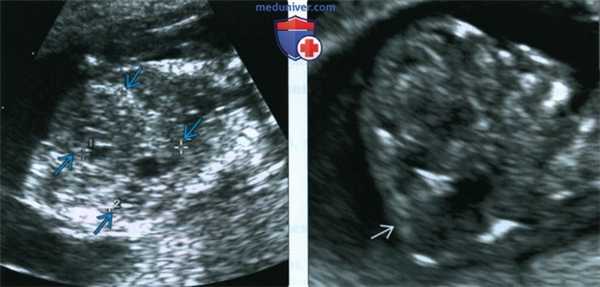

(Слева) Тот же плод. УЗИ брюшной полости, фронтальная плоскость. С обеих сторон определяются увеличенные кистозно-измененные почки. Необходимо помнить, что объем амниотической жидкости в I триместре может быть в норме, даже несмотря на тяжелое двустороннее поражение почек.

(Справа) Во время скринингового УЗИ плода в I триместре, выполненного во время последующей беременности у той же женщины, обнаружено энцефалоцеле. Синдром Меккеля-Грубера имеет аутосомно-рецессивный тип наследования, риск повторного возникновения составляет 25%.